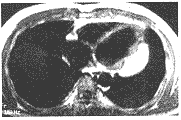

左心室室壁脂肪瘤致顽固性室性心律失常一例

患者男 ......